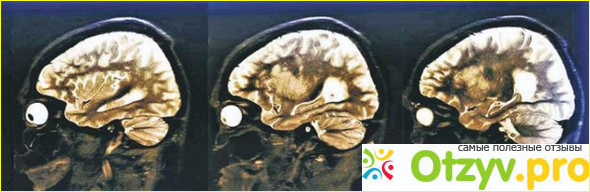

"Times New Roman", Times, serif; font-size: 18px; font-style: normal; font-variant-ligatures: normal; font-variant-caps: normal; font-weight: 400; letter-spacing: normal; orphans: 2; text-align: start; text-indent: 0px; text-transform: none; white-space: normal; widows: 2; word-spacing: 0px; -webkit-text-stroke-width: 0px; background-color: rgb(255, 255, 255); text-decoration-style: initial; text-decoration-color: initial;">Откладывание бета-амилоидного белка в мозге приводит к возникновению болезни Альцгеймера. Белки устраняются из мозга во время сна, однако алкоголь может наладить этот процесс и во время сна / Изображение: ZEPHYR

Ученые обратили внимание на исследование новообнаруженного глимфатичнои системы. Возможно, проблема - повреждена система очистки мозга? Она активна во время сна, а некоторые исследования предполагают, что долговременные расстройства сна могут приводить к развитию болезни Альцгеймера, вызывая накопление бета-амилоидного белка.

Когда мы спим, нейроглия сокращается и увеличивает межклеточное пространство на 60%. В мозговой ткани возникают «маленькие дыры», поэтому спинномозговая жидкость, вымывает токсины, может проникать в мозг в большем количестве. Мусором, который нужно «вымести», есть и накопления бета-амилоидного белка.

2012 ученые исследовали, что с этим белком происходит. Его обозначали флюоресцент и наблюдали за его передвижением. Выяснилось: у мышей во время сна этот белок вымывался вдвое быстрее, чем в состоянии бодрствования.